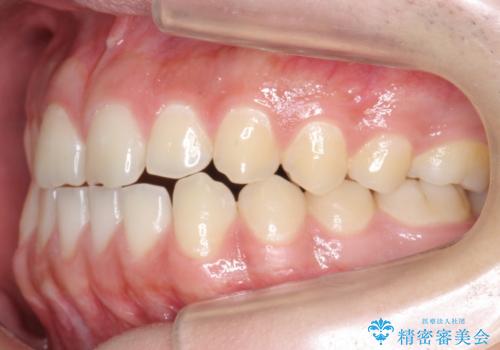

前歯のすきま 受け口 インビザラインで

- 前歯のすき間を気にして来院。

受け口もあり、前歯が端同士であたる、切端咬合となっていました。

下の歯のすき間を閉じて上の歯の内側に入るように位置付けました。

すき間もきれいに閉じ、満足していただきました。

上の前歯は下の歯と直接へりが当たっていた状態(切端咬合)だったため、形がいびつだったのは、わずかにやすりがけをして整えました。